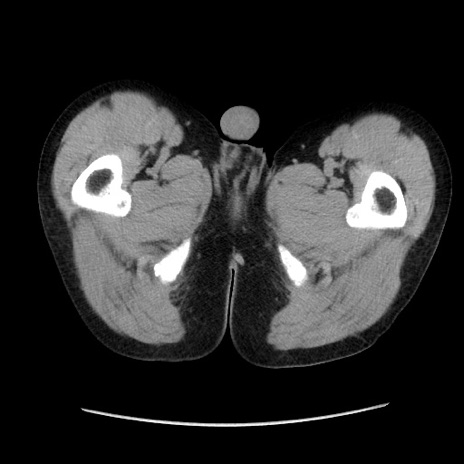

症例37(横断像)

【症例】40歳代 男性

【主訴】腹痛

【現病歴】4時間ほど前に電車に乗車中に臍部上より腹痛出現。徐々に増悪し起立困難となり、救急外来受診。生ものは数日食べていない。今朝お雑煮を食べた。

【身体所見】BT 36.8℃、BP 117/84mmHg、HR 91/min、SpO2 97%、苦悶様、腹部:臍上部広範囲圧痛あり、反跳痛±

【データ】WBC 8100、CRP 0.03